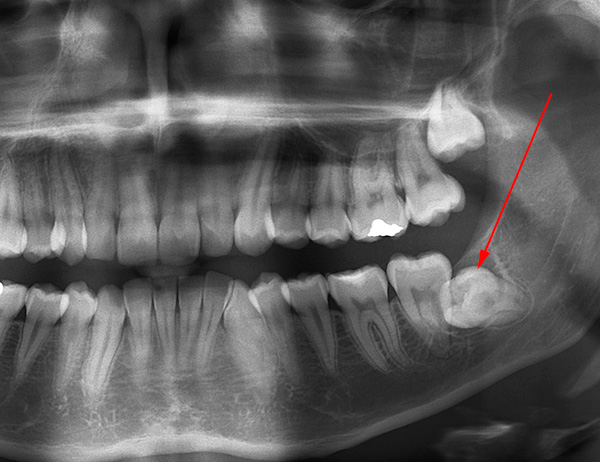

Il seguente è un esempio di un dente del giudizio orizzontale nella mascella: